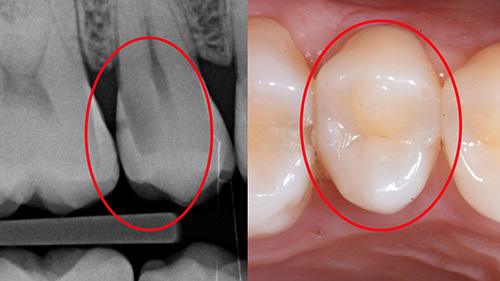

Molti problemi e insoddisfazioni derivano da una diagnosi imprecisa o poco approfondita per mancanza di tempo dedicato alla prima visita e raccolta dati insufficiente (foto, radiografie, tac).

La Prima Visita è un passaggio decisivo e necessita di cura e strumentazione adeguata.

Otturazioni semplici o ricostruzioni complesse o intarsi sempre eseguiti con diga di gomma.

Devitalizzazioni precise guidate dal supporto della radiologia tridimensionale.

Più denti naturali, meno impianti

In SoriDent siamo convinti che il miglior impianto sia sempre il tuo dente.

Per questo adottiamo un approccio conservativo e personalizzato, che punta a recuperare e mantenere gli elementi naturali ogni volta che è possibile, anche quando appaiono gravemente compromessi.

Grazie a tecniche avanzate di odontoiatria conservativa, protesi e parodontologia, restituiamo funzionalità ed estetica al sorriso senza ricorrere subito alla chirurgia implantare.

Questo significa cure meno invasive, tempi di recupero più rapidi e un risultato più naturale e duraturo.